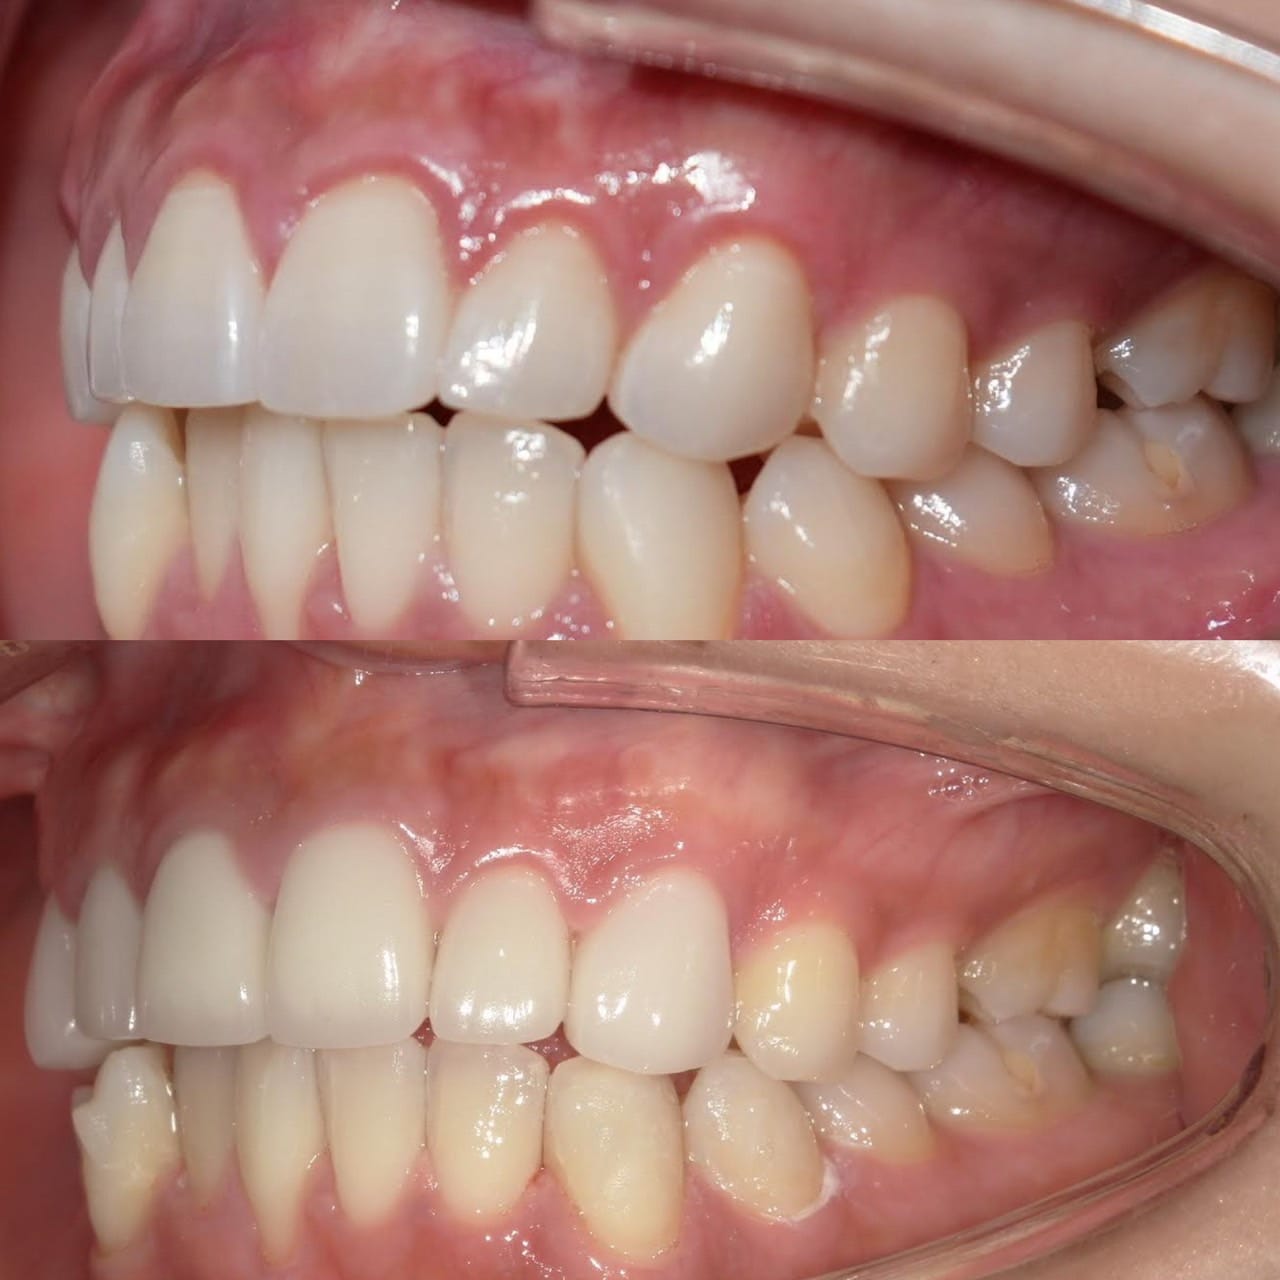

Case009

前医でマウスピース矯正をしたものの、うまくいかなくて当院にお越しくださった患者様です。

もう時間をかけたくないとの主訴だったので、マウスピース矯正ではなくセラミック矯正で治しました。

クリーニング+セラミック矯正+ホワイトニング

来院回数 3回(初回のカウンセリング含む)

初診時よりとても綺麗になって満足して頂きました。

担当:理事長 佐藤悠野

Case008

前医でマウスピース矯正を試してみたものの上手くいかず、当院にお越しくださった患者様です。

もう時間をかけたくないとの主訴だったので、マウスピース矯正ではなくセラミック矯正で治療しました。

初診時よりとても綺麗になり、満足して頂けました。

かぶせもの:セラミック

治療費:687,500円(エアフロー+セラミック矯正+ホワイトニング)